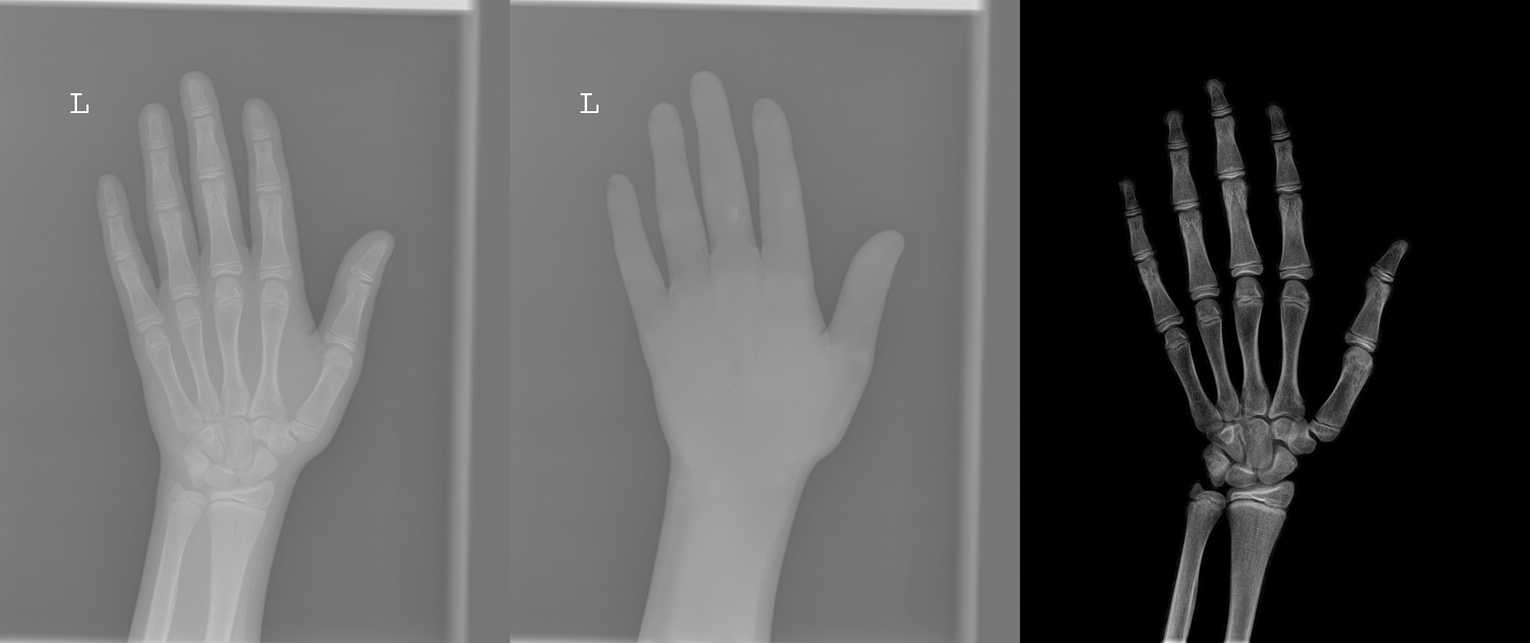

We performed three experiments for our method. First, we perform our method on several X-ray images, showing our method is not restricted by specific imaging objects. Second, we compared our method with image enhancement method and dehazing method, showing that our modification of the original dehazing indeed helps in this task. Third, we perform our method on a hand X-ray image dataset, showing its effectiveness and efficiency.

Several results from our method are shown in Fig. 7. The left column is the original input image. The right two columns are the soft tissue and bone image, respectively. It can be told that the soft tissue image is smooth as we assumed. Meanwhile, the bone image has better image contrast as desired. Moreover, our method can reach real-time performance on these X-ray images. The running time of our method on these images is reported in Table I.

In the third experiment, we applied our method on a hand X-ray image data set (RSNA), which contains more than 10,000 hand X-ray images. And the image has high resolution (usually larger than ). These images are collected from clinical applications. Therefore, we can apply our method on these practical images, showing the efficiency and effectiveness of our method on real high resolution images.

In each panel of Fig. 10, the input image (left) is decomposed into soft tissue (middle) and bone image (right) by our method. Although we only show the first ten images from the data set, the results for the rest images are similar.

The bone images have better image contrast since the parameter is theoretically guaranteed. Such enhancement can also be directly told by radiologists. Such enhancement is good for bone diagnosis in practical applications.

Moreover, the running time of our method on such high resolution images is less than half second in the MATLAB language on a laptop. Therefore, it can achieve higher performance on a better hardware in real applications. If higher performance is required, our model can be solved by the parallel Laplace equation solver on a modern graphic process unit (GPU), which usually has thousands of cores.